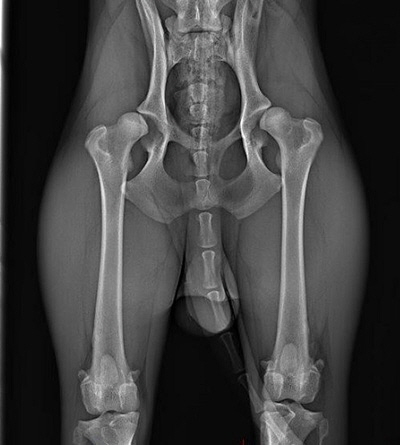

gesund_HD_hund